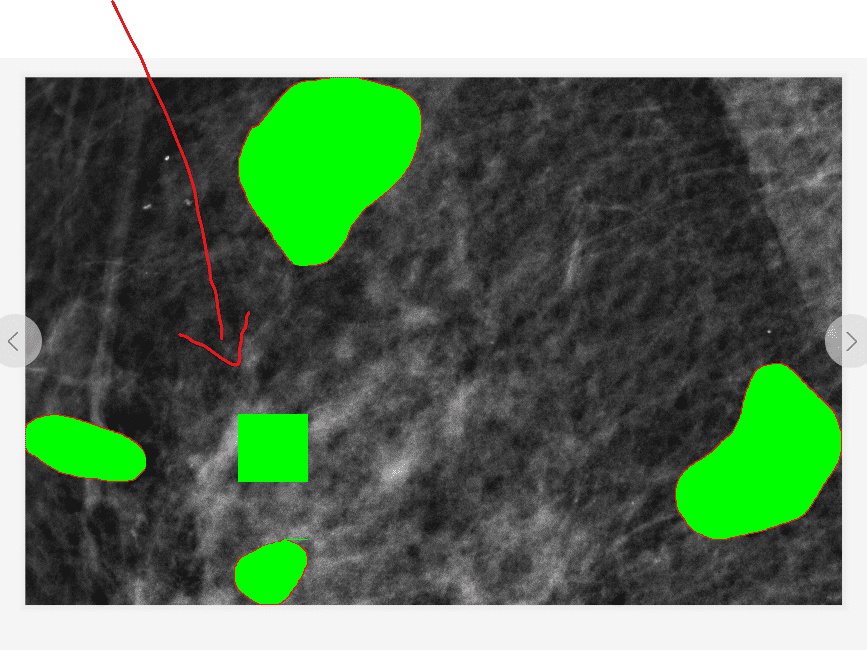

正文:算法的思想很简单,遍历图片每一列,通过色差判断是否遇到标记圈,将坐标全部记录,对每一列的坐标都进行最小行和最大行记录,确定每一列的最小和最大的坐标,然后上色(类似opencv的fillPoly的实现,但是细节有些区别),只是这样效果并不好,将图片旋转90度,再做一边,将两个图片的结果放在一起做与操作,得到结果就能很好的处理多圈的标记问题和多算面积的问题(比如上面的08-LM),

做两遍的效果图

可以看到效果非常不错,但是依旧有个别图像有问题,比如十字分布的,